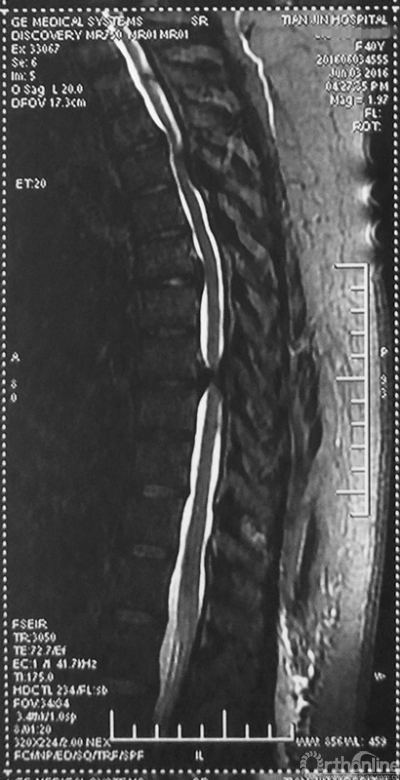

家人曾带她辗转当地治疗,因病情复杂没有得到有效的治疗,于是慕名找到天津医院脊柱外科二病区主任苗军博士诊治,当苗军主任看到躺在担架上的刘女士痛苦的表情和渴望健康的眼神,他决定收她入院为其进行手术治疗。入院检查发现,刘女士患有多节段胸椎管狭窄症,以胸8-9节段严重,椎管狭窄达80%,脊髓已严重变性。

术前MRI